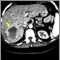

Es un tumor benigno del hígado compuesto de vasos sanguíneos ensanchados (dilatados).

Un hemangioma hepático es el tumor benigno más común del hígado. Se cree que es una anomalía congénita.

El hemangioma hepático por lo regular no se descubre hasta que se toman imágenes de diagnóstico del hígado por alguna otra razón. Si un hemangioma cavernoso se rompe, el único signo puede ser un hígado agrandado.